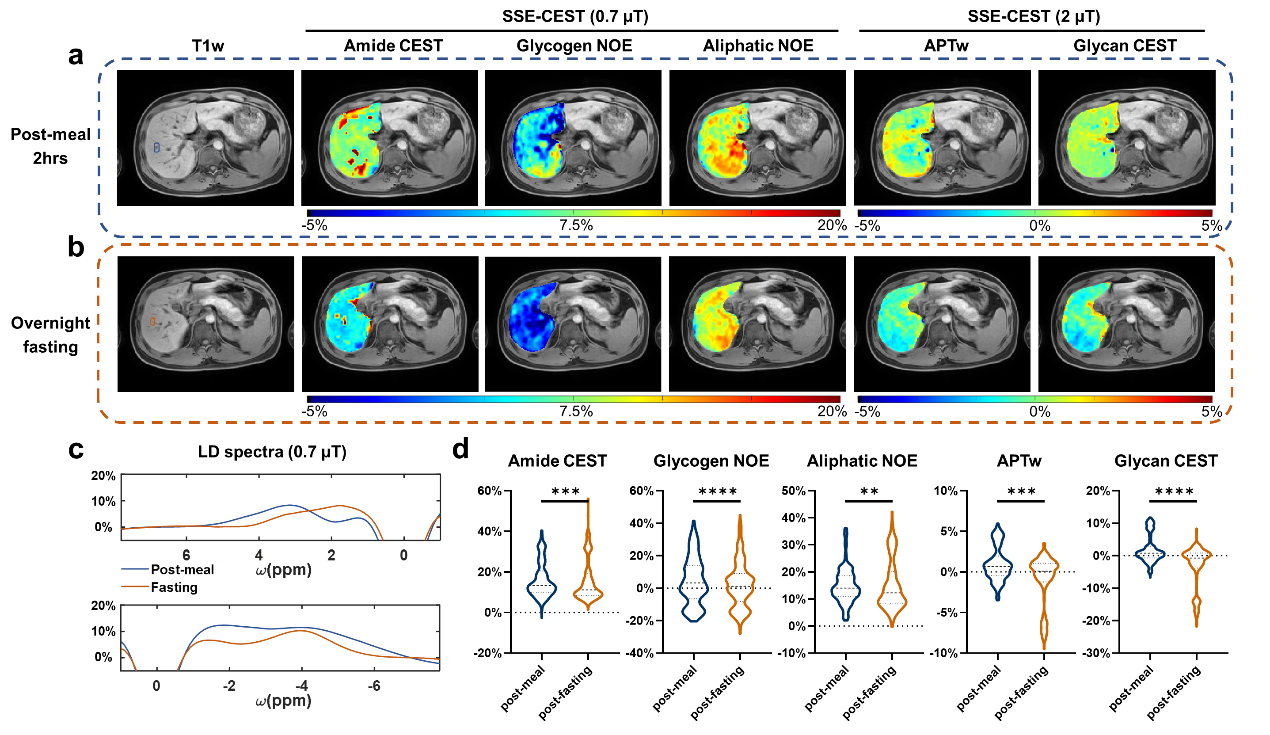

单次屏气SSE-CEST可同时获得酰胺CEST(3.5 ppm)、糖原NOE(-1.2 ppm)、脂肪族NOE(-3.5 ppm)、APTw及羟基CEST(1.2 ppm)等多种对比。在空腹实验中,禁食12小时后肝脏酰胺CEST、糖原NOE、脂肪族NOE、APTw及羟基CEST均显著下降(p值均<0.01),频谱变化清晰可辨。

图4 SSE-CEST 技术用于评估禁食实验期间肝脏的代谢变化